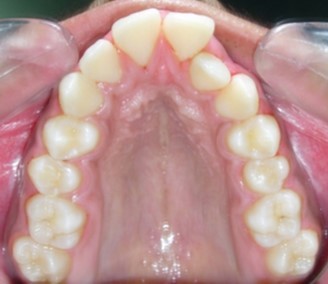

Figure 1g.Pre-treatment intra-oral-Upper occlusal

The maxillary arch was V-shaped with severely proclined and rotated maxillary incisors with a palatally placed 12. The mandibular arch was U-shaped with severe crowding of mandibular incisors, with 43 partially erupted and buccally placed with transpositioned 42 and 43, with 42 mesiolingually rotated, 33 distolingually rotated and 34 distolingually rotated and buccally placed.

Severe increase in overjet and deep bite were both observed. The maxillary midline coincided with the skeletal midline but the mandibular midline was shifted to the right side by 1 mm. Bilateral maxillary posterior crossbite was also observed. On right side the molar relation was Class I and on the left side it was Class II. The canine relation was Class II on the left side and the curve of Spee was increased.

Figure 10a.Pre aexpansion - maxillary arch